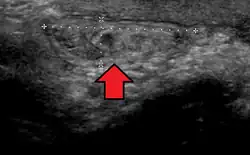

Ultrasound showing an inguinal hernia

By far the most common hernias (up to 75% of all abdominal hernias) are inguinal hernias, which are further divided into the more common indirect inguinal hernia (2/3, depicted here), in which the inguinal canal is entered via a congenital weakness at its entrance (the internal inguinal ring), and the direct inguinal hernia type (1/3), where the hernia contents push through a weak spot in the back wall of the inguinal canal. An indirect inguinal hernia and a direct inguinal hernia can be distinguished by their positioning in relation to the inferior epigastric vessels. An indirect hernia is situated laterally to these vessels, whereas a direct hernia is positioned medially to them. Inguinal hernias are the most common type of hernia in both men and women. In some selected cases, they may require surgery.